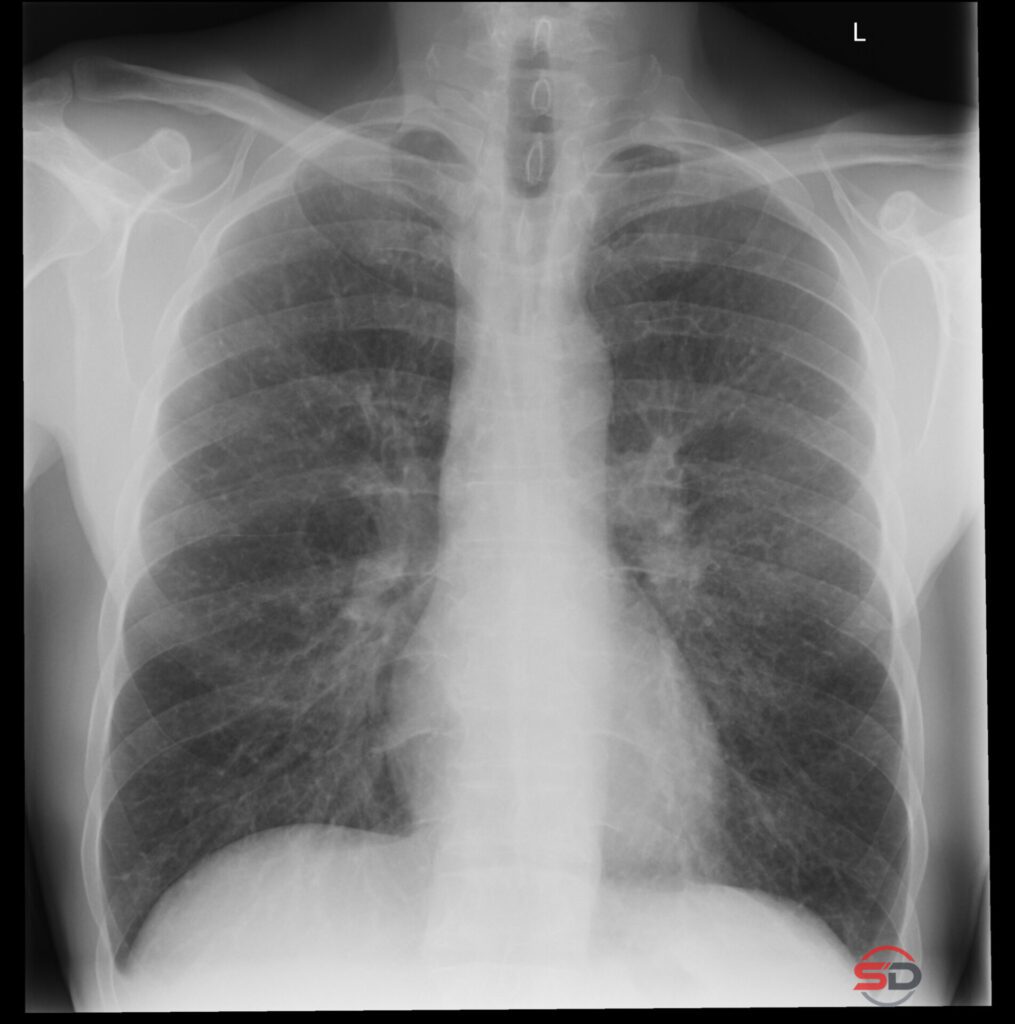

Wie zuverlässig sind Grössenmessungen im Thoraxröntgen?

Das konventionelle Thoraxröntgen gehört zu den am häufigsten durchgeführten radiologischen Untersuchungen. Neben der Beurteilung des Lungenparenchyms, der Mediastinalstrukturen und des […]